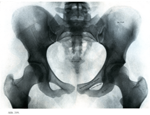

7. 骨盤

1. 下肢帯骨の連結